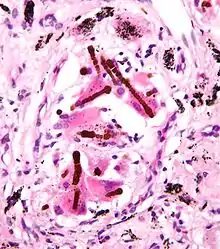

- Malignant mesothelioma: an aggressive and incurable tumour arising from mesothelial cells of the pleura (the lining of the thoracic cavity).